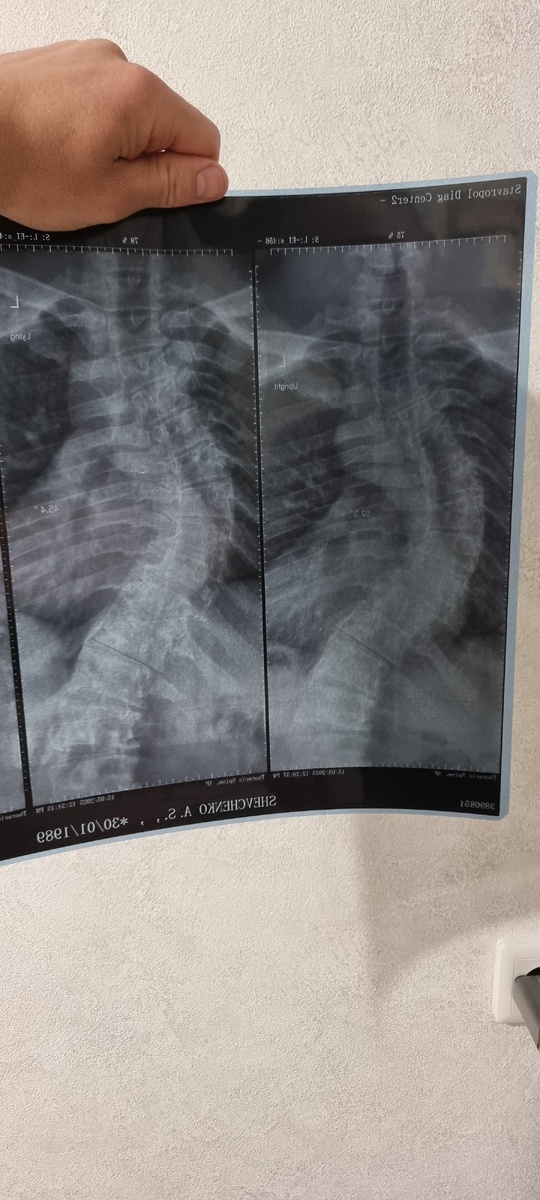

В 14 лет врач сказал мне: "С такими изгибами позвоночника тебе нельзя даже отжиматься". В 34 я выиграл чемпионат по пауэрлифтингу. Это не мотивация — это предупреждение. ПРОВЕРЬ СЕЙЧАС: Наклонись вперед. Если ребра с одной стороны выступают сильнее — закрой эту статью и иди к врачу. Твой сколиоз уже опасен. 3 СМЕРТНЫХ ГРЕХА ТРЕНИРОВОК ПРИ СКОЛИОЗЕ 1. "Качай пресс как все" Классические скручивания при 4 степени сколиоза = гарантированная грыжа через 3 месяца. Я научился делать их... без движения позвоночника. Секрет — в изометрическом напряжении, которые мне позволили укрепить мышцы и создать прочный мышечный корсет, а уже после я стал двигаться дальше. 2. "Растягивайся для гибкости" Моя ошибка: пытался "выпрямить" спину растяжкой. Результат — микроразрывы связок. Спасение — активная мобилизация и постоянная концентрация на правильном положении тела. 3. "Боль — это прогресс" При сколиозе "правильная" боль = сигнал STOP. Мой лайфхак: если боль симметричная — можно пр